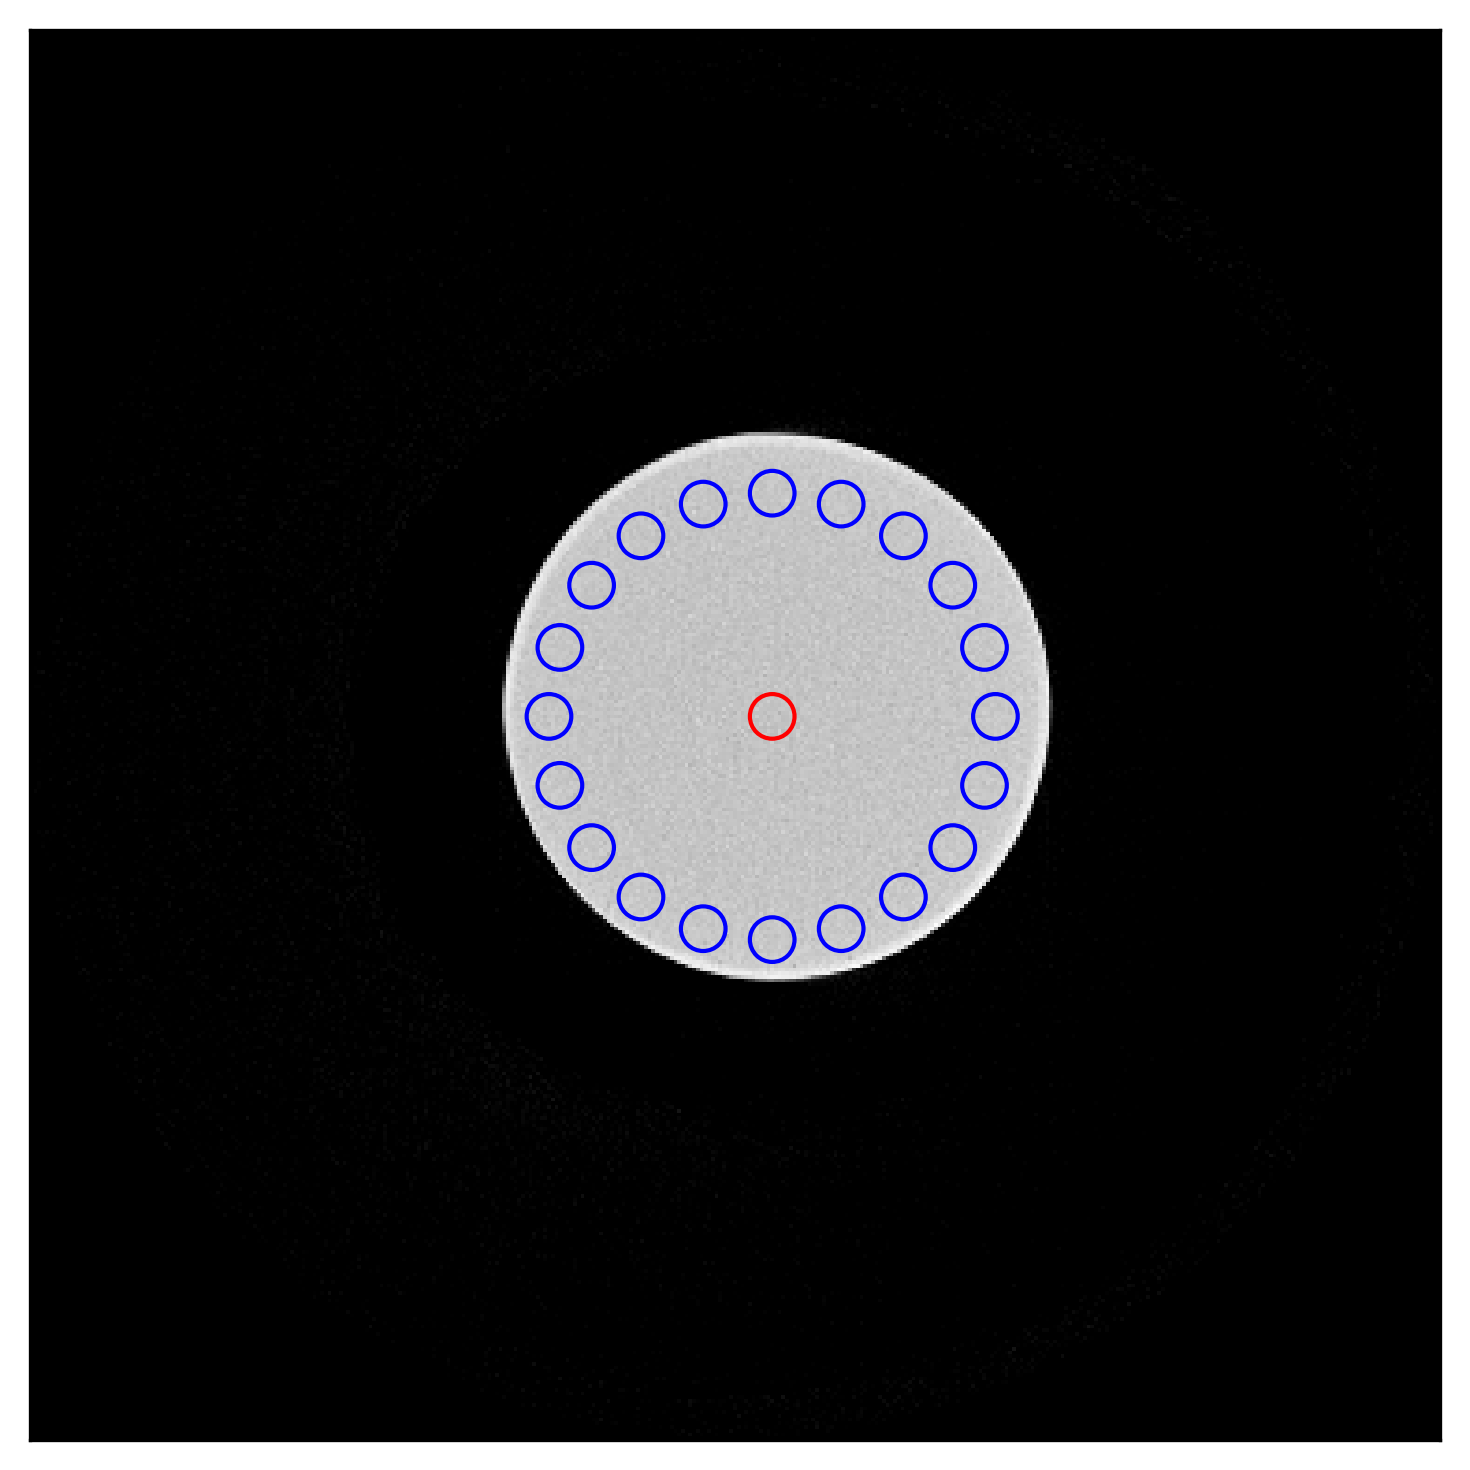

Refer to caption

(a) Water jar axial image showing the location of the central ROI (red) and 20 ROIs (blue) in the periphery, used to calculate image uniformity.

(a) Uniformity (HU) calculated for various methods for the selected ROIs from the water jar scan.

method uniformity

uncorrected 118

net-320×256320\times 256 47

net-160×128160\times 128 18

net-80×6480\times 64 29

net-40×3240\times 32 18

net-20×1620\times 16 27

Figure 8: Image uniformity in the corrected images compared for the different methods.

Further, we compared the scatter estimation performance of five different networks, trained with five input sizes for the simulated projections. The net-40×3240\times 32 outperformed all the other networks showing least MSE (0.134±0.0090.134\pm 0.009) and comparable MAPE (3.85±0.103.85\pm 0.10) with only 310 MB of GPU memory, processing a batch size of 64 in just under 6 ms. In comparison, net-320×256320\times 256 took 90 ms with 3.9 GB GPU memory and had worse MAPE (4.42±0.184.42\pm 0.18 and MSE (0.20±0.0140.20\pm 0.014). Similar results were obtained for the simulated reconstructions after the scatter correction. Specifically, net-40×3240\times 32 had second lowest RMSE (8.96±2.908.96\pm 2.90), which was better than the RMSE (9.66±2.299.66\pm 2.29) of net-320×256320\times 256. However, net-160×128160\times 128 had slightly better RMSE of 8.85±2.928.85\pm 2.92. It is clear that the smaller input size significantly reduces the computational requirements while maintaining acceptable error rates. Which shows that the net-40×3240\times 32 configuration offers a good balance between performance and resource efficiency. Additionally, the uniformity is shown for the water jar and water bottle scans in Fig. 8. The difference between the uniformity values of the uncorrected images is significant, with the uniformity being 118 HU for the large water jar and 8 HU for the small water bottle. This discrepancy results from the large amount of scatter in the larger water jar compared to the smaller water bottle. An interesting observation is that while the neural network-based methods improved the uniformity in the water jar scan (18 HU), the uniformity worsened for the water bottle (16 HU). This can be attributed to the over-correction in the water bottle compared to the water jar since the training data did not include such small objects. Nonetheless, the net-40×3240\times 32 achieved comparable results to the other best performing networks for both scans.